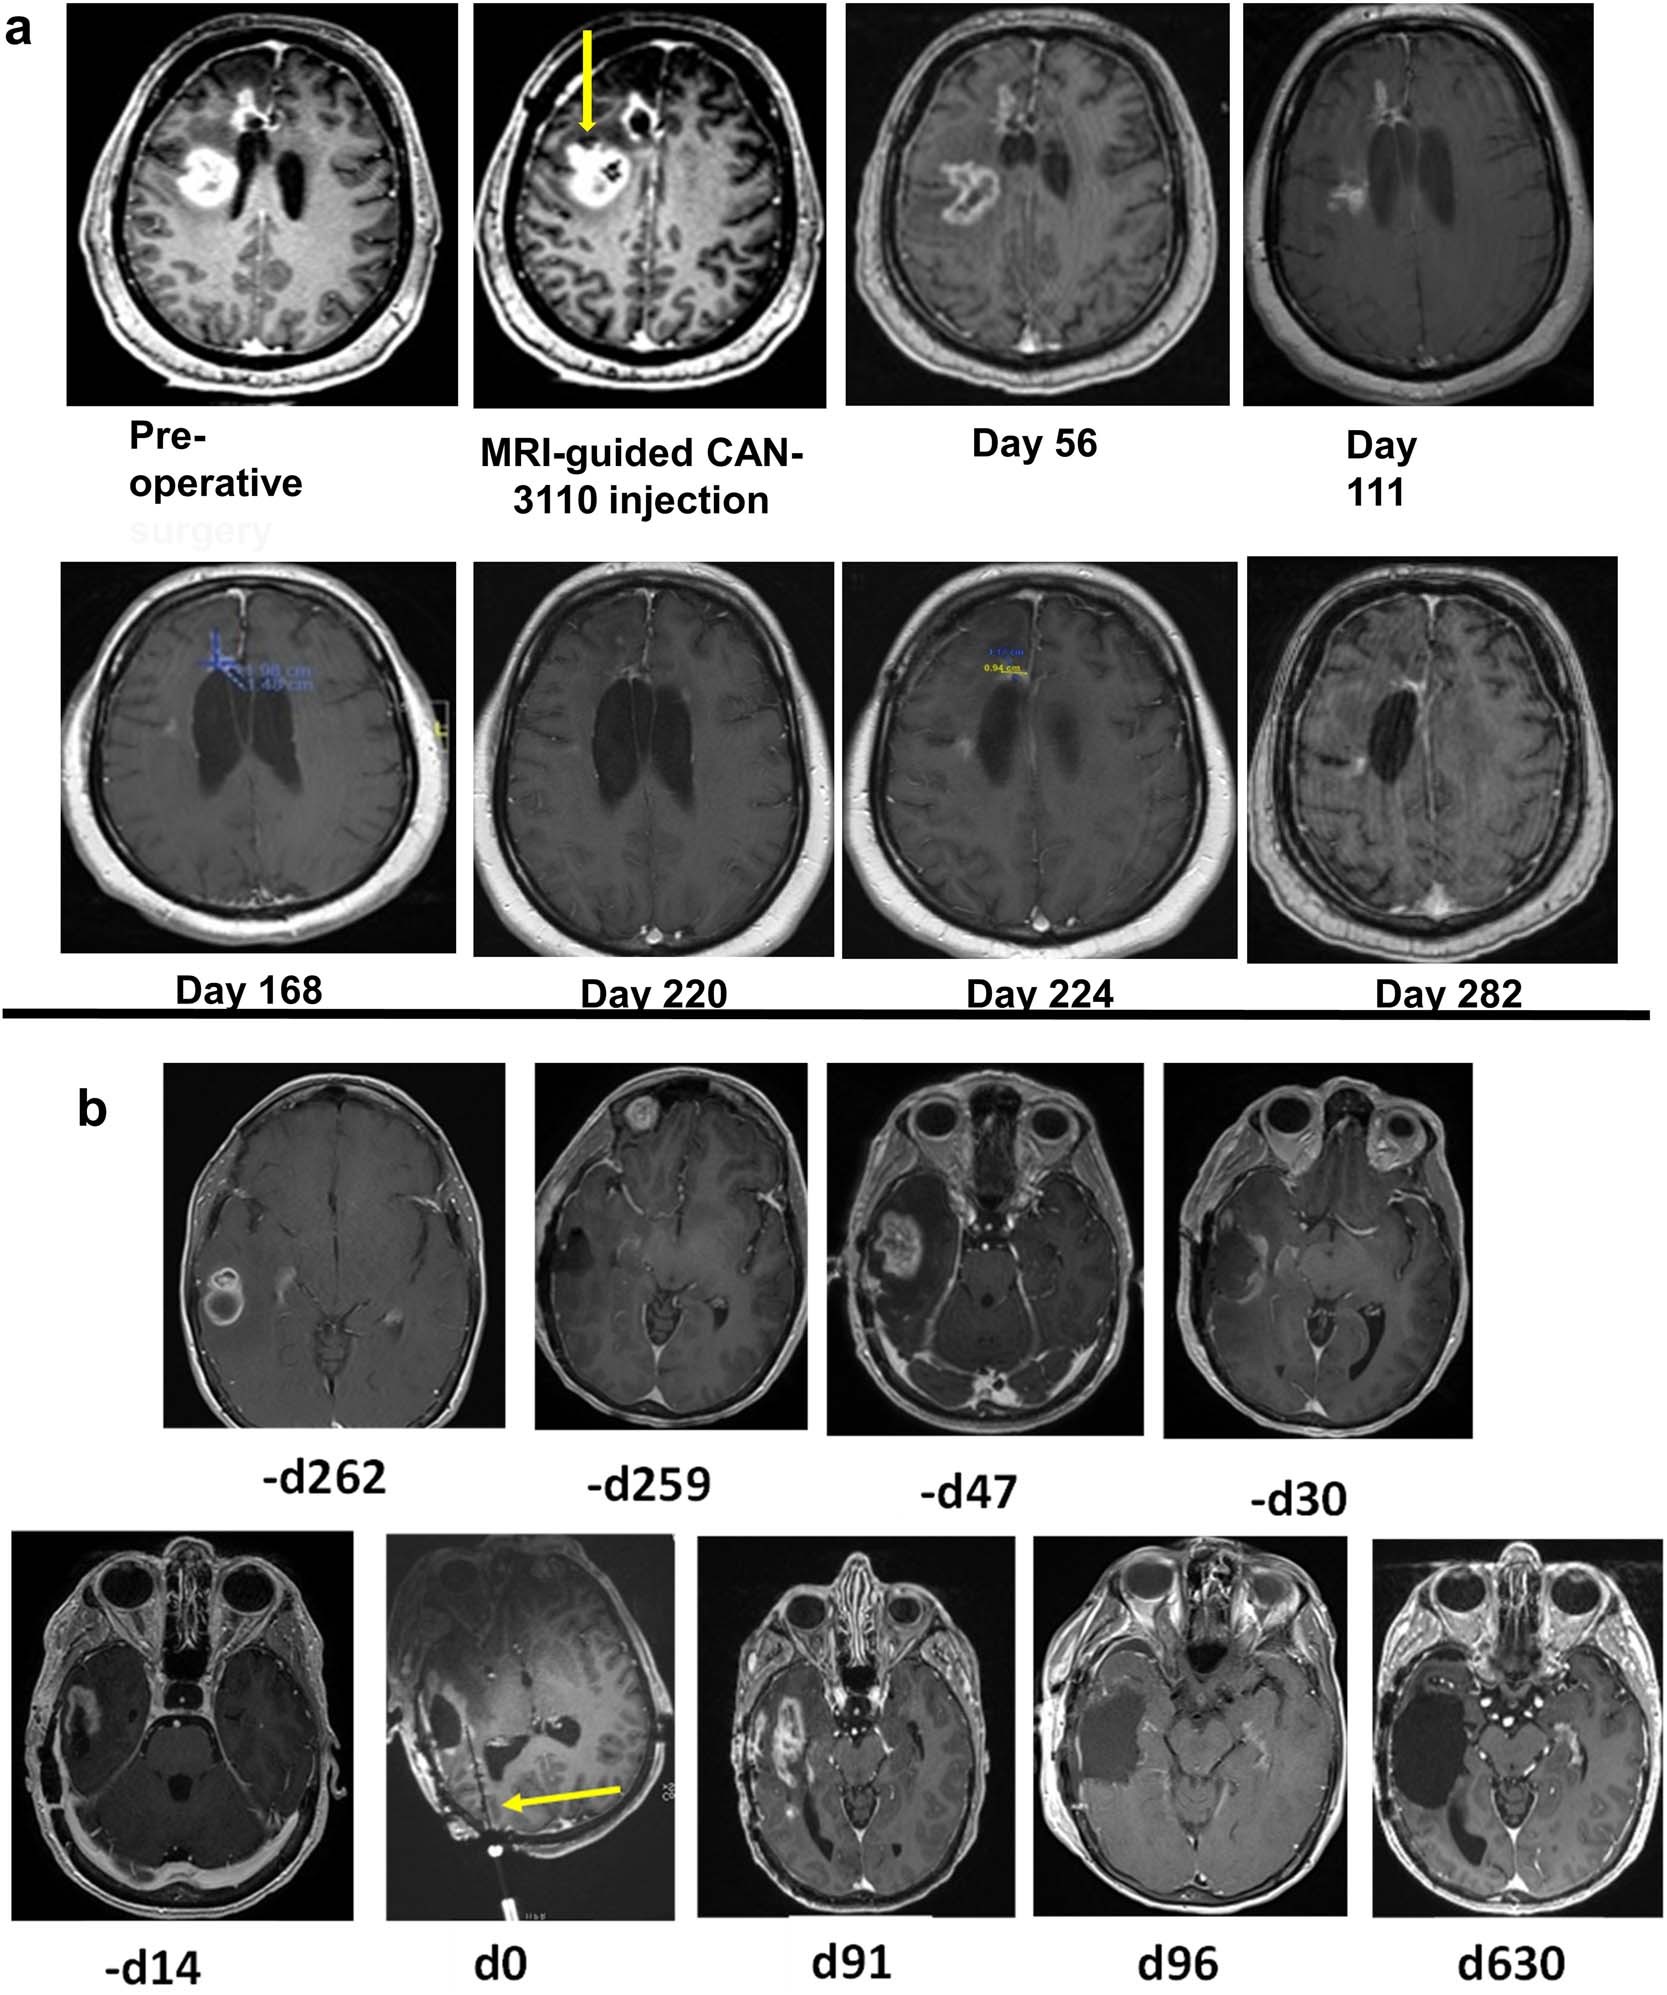

Extended Data Fig. 4: (related to Sub-Heading, HSV1 serology predicts efficacy) MRI imaging responses to CAN 3110.

(a) Complete response in a multifocal GBM subject. Subject 007 (56 year old caucasian man, IDHwt GBM) had an initial right frontal GBM resected. After completion of standard of care radiochemotherapy, the right frontal lesion grew back and a second new lesion posterior and periventricular also appeared (Pre-operative MRI). The subject underwent injection of CAN-3110 (106 pfus in 1 ml) solely into the second new lesion (indicated by yellow arrow in MRI-guided CAN-3110 injection label). Serial MRIs on day 56, 111, 168, 220, 224 and 282 are shown. No other treatments and no dexamethasone were administered during this time, during which the patient experienced full time employment, travel and enjoyment from significant family events. At the 349 day mark, a new separate biopsy-proven recurrence in the right basal ganglia leading to a progressive hemiparesis and hemiplegia prompted the subject to seek hospice care and eventual demise. (b) Durable response in a right temporal GBM subject. Subject 021 (61 year old caucasian female, IDHwt GBM) had an initial GBM diagnosed 262 days (-d262) before CAN-3110 injection. After craniotomy and tumour resection (-d259), she underwent standard chemoradiation and then treatment with temozolomide for IDHwt GBM with methylated MGMT promoter. The tumour recurred (-d47) and she underwent a second subtotal resection (-d30), but because of visible rapid progression (-d14), she was enrolled in the CAN-3110 trial. On d0, she received single injection of 108 pfus (the MRI-compatible injection needle is indicated by the yellow arrow). On d91, MRI appeared to show progression and she was brought back to surgery for resection of the mass with postoperative MRI showing a gross total resection (d96). Histology and immunohistochemical staining showed a mixture of CD8+, CD4+, CD20+ lymphocytes and tumour (see Extended Data Fig. 6d, panels labelled with #21). The subject then remained tumour free for the next 630 days (d630), which was the time of her last MRI. Unfortunately, she passed as the passenger of a motor vehicle accident on d717. The subject’s personal story is shared in the supplementary video 1 with consent of her family.